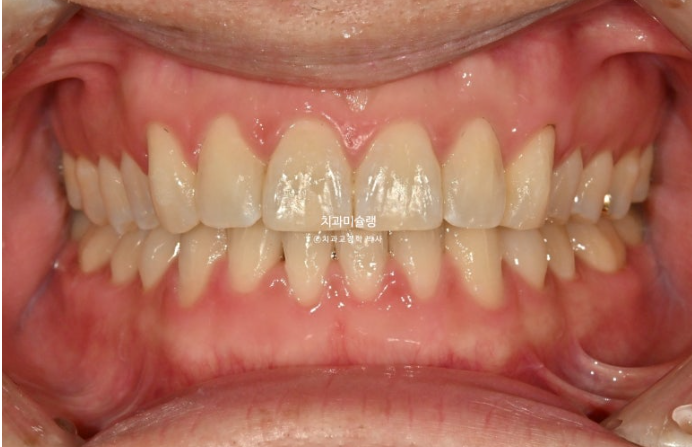

앞니 높낮이가 맞아지면 들쑥날쑥 했던 잇몸라인은 자연스럽게 맞아집니다.

앞니만 교정하는 부분교정이기에 어금니 교합은 그대로 유지됩니다.

이제 전후 비교 보겠습니다.

총 치료기간은 6개월 입니다.

25.04~25.10

중심선 불일치는 부분교정의 한계점으로 그대로 덧니를 포함한 배열만은 완벽합니다.

특히 아래 앞니 중 튀어나와있던 파란 화살표 앞니는 배열 과정에서 잇몸라인도 자연스럽게 주변과 맞아집니다.

환자분이 투자한 기간과 비용 대비 아주 만족스러운 결과입니다.